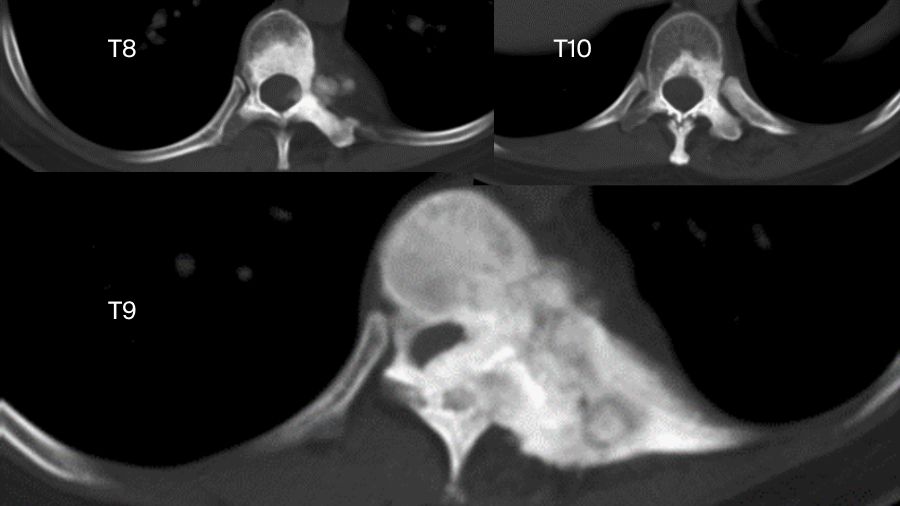

But sometimes things are more complicated. Another case involved a 33-year-old female. The chest X-ray examination found an osteogenic spinal lesion. The CT scan showed osteolytic lesions of T9 left vertebral body, facet joints and rib, with extensive reactive bone formation.

There was obvious spinal cord compression, and the PET/CT revealed extensive uptake.

We did a CT-guided biopsy. Although we consulted the result in three hospitals, the pathologists failed to give us a definite diagnosis, whether it was osteoblastoma or a low-grade osteosarcoma.

So, we treated it as if it was malignant. We did an anterior-posterior approach sagittal en bloc resection of the T8 to T10. In the anterior approach, we dissected the tumor. In posterior approach, we transected the body with an ultrasonic cutter. We resected three segments en bloc. The margin was sufficient, not only pathologically, but also by CT scan.

The postoperative pathological diagnosis is still unclear. The pathologists gave us four diagnoses: osteoblastoma, epithelioid osteoblastoma, low-grade osteosarcoma, or even osteomyelitis.

Nevertheless, the patient was doing well in the 2-year follow-up. There is no recurrence.